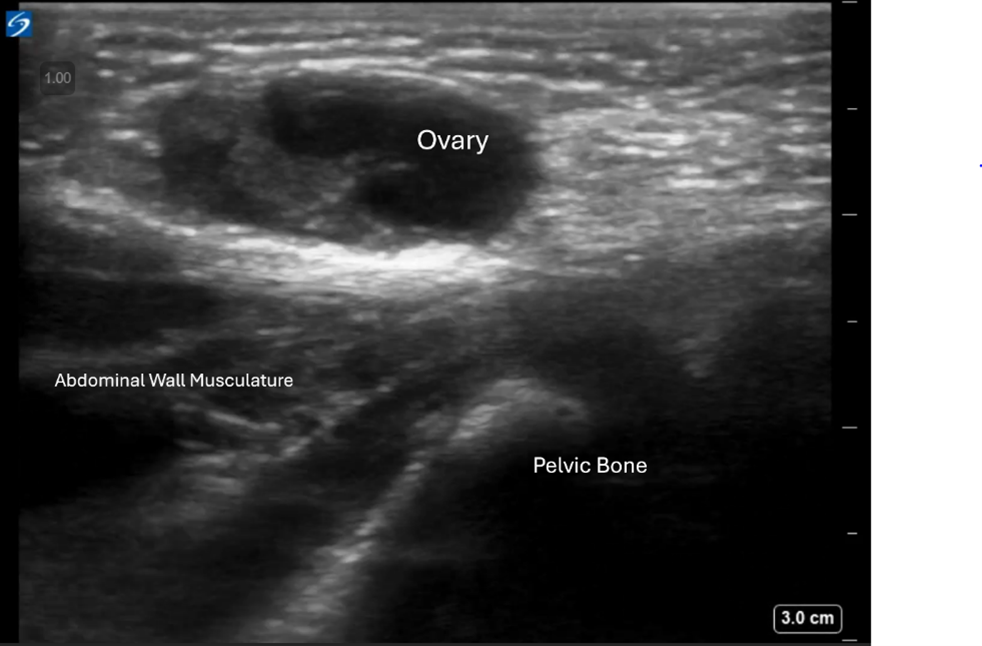

Image 3: Transverse view. The ovary is confirmed to be within the hernia sac and superficial to the abdominal wall musculature.

The contralateral (left) pelvis was scanned, showing a similar structure consistent with a normal-appearing ovary in its expected location. On returning to the affected side, the right ovary was absent from the pelvis. The inguinal mass was identified as the right ovary, herniated into the inguinal canal.